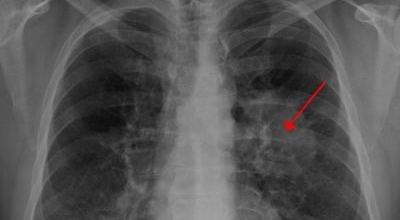

5. 폐암 초기증상 - 호흡곤란

폐암 초기증상엔 호흡곤란이 나타나게됩니다. 폐암 환자의 약 50% 정도가 숨이 차다고 느끼게 될 수 있다고 하네요. 이는 암 덩어리가 커져 호흡이 가쁘다고 느낄 가능성도 있지만 폐암으로 인한 폐허탈, 상기도폐색, 흉막 삼출 등등이 호흡곤란을 유발하기도 해요. 평상시와 다르게 숨이 차는 느낌이 들면서 숨을 들이쉬고 내쉴때 쌕쌕 거리는 소리나 나온다면 폐암 초기증상을 의심해 볼 수 있습니다.